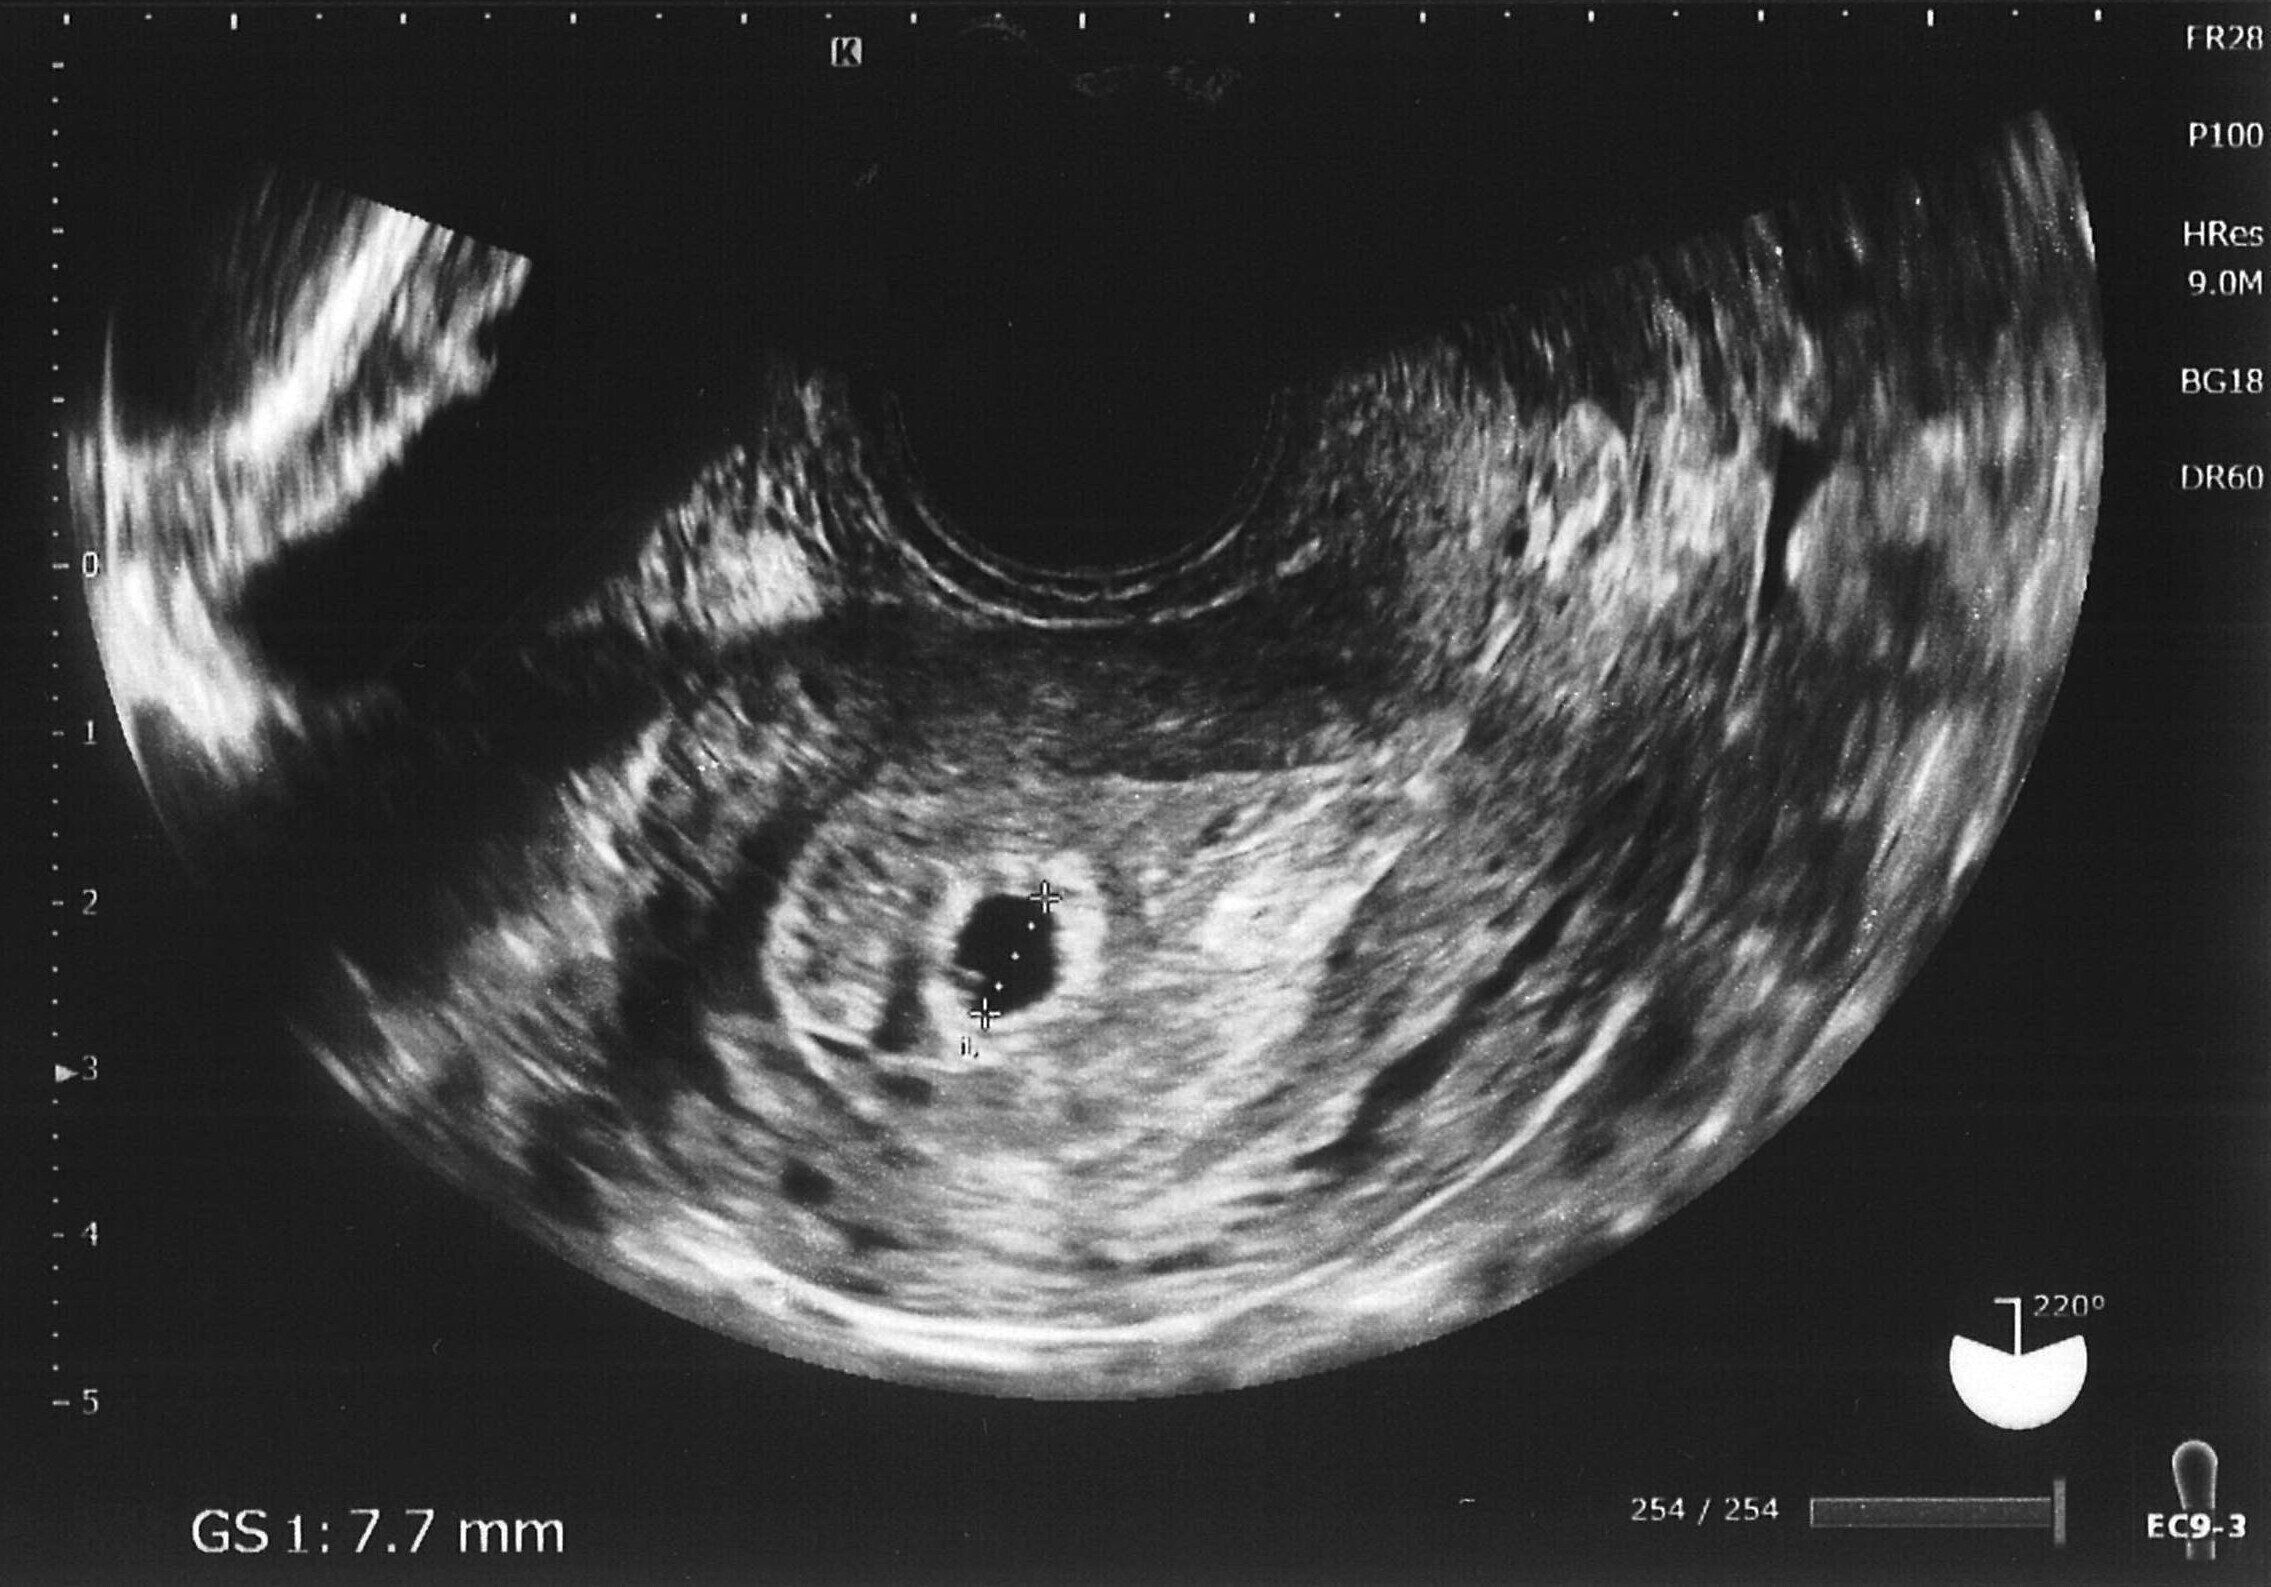

島田 そうです。ちょうどゴールデンウィーク前から体がだるく、ずっと眠かったんです。おなかも痛くて何か変だなと思っていました。妊娠検査薬を買って調べたところ、妊娠を示す線がくっきりと出たんです。すぐに病院に行ったところ着床していると言われました。検査薬の結果でわかってはいたけれど、改めて告げられ、びっくりしました。私は39歳になっていました。ずっと子どもは欲しかったし、年齢的に妊娠するのは最後のチャンスかもしれないとも思いました。

ただ、そのときは時期が早すぎて赤ちゃんの心拍が確認できませんでした。「ゴールデンウィーク明けにもう一度来てください」と言われ、連休中は悶々(もんもん)として過ごしました。